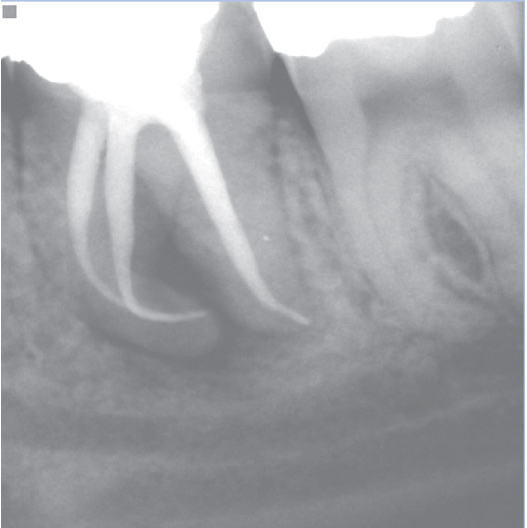

Before

Before Root Canal treatment